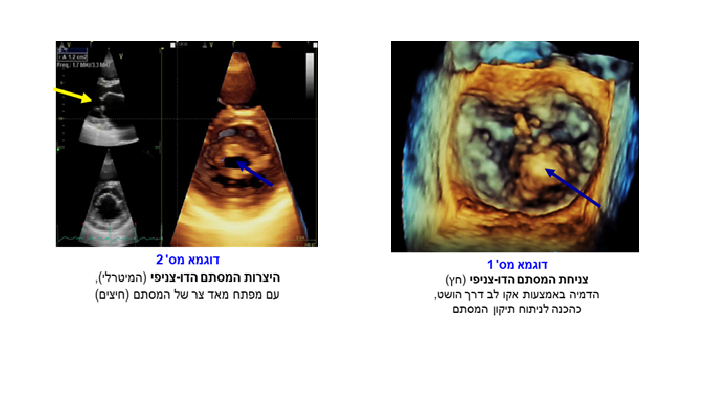

אקו לב דרך הושט, (TEE (Trans-esophageal echocardiography היא בדיקה המבוצעת באינדיקציות מאד ספציפיות, לרוב כהשלמה לבדיקת אקו דרך בית החזה. הדמית הלב מתבצעת באמצעות מתמר המוחדר לתוך הוושט (בדומה לבדיקת גסטרוסקופיה). קרבת הוושט לחלקו האחורי של הלב מאפשרת הדמיה לפרטי פרטים של חלקי הלב הקרובים לוושט: עליות הלב והמחיצה הבין-עליתית, מסתמי הלב (בעיקר המסתם הדו-צניפי, המיטרלי) ואבי העורקים.

ג. צניחת המסתם הדו-צניפי (מיטרלי) עקב שינויים ניווניים או גנטיים ברקמת המסתם (סיבה מאד נפוצה לדליפת המסתם המיטרלי).

בדיקת האקו, אשר מתבצעת דרך בית החזה ו/או דרך הוושט, היא הבדיקה העיקרית המשמשת להערכות מגוון מחלות מסתמי הלב והיא הפכה במהלך השנים לאמת המידה האבחנתית בכל הנוגע למחלות מסתמיות.

בדיקת האקו יכולה להדגים את מבנה המסתמים ותפקודם, הן באופן איכותי והן באופן כמותי (מדידת מפלי לחצים ע"פ מסתם מוצר, הערכת הלחצים במדורי הלב השונים, חישוב שטח מפתח מסתם מוצר והערכת נפח הדליפה של מסתם דולף), ללא צורך בבדיקות נוספות, כגון צינתור לב, ברוב המוחלט של המקרים.